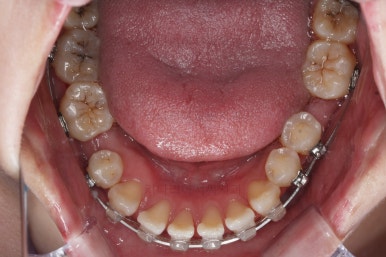

브라켓을 부착합니다.

이번 환자분이 선택하신 장치는 데이몬 클리어라고 하는 자가결찰 세라믹 장치인데요.

일반적으로 흔히 아시는 클리피씨 장치에 비해서 철사를 잡아주는 뚜껑까지 세라믹으로 되어 있어서 아마도 현존하는 세라믹 장치 중에서는 가장 심미적인 장치라고 볼 수 있습니다.

대신, 세라믹으로 되어 있다보니 강도 때문에 부피는 조금 더 커진다는 단점은 있긴 합니다.

치열이 매우 가지런해졌고, 아래 앞니 사이 틈새도 점점 오므려져 가고 있습니다.

발치 공간을 적극적으로 줄여 나갑니다.

이 과정에서 입매, 앞니 각도, 정중선 등을 신경 써줍니다.

아무래도 상하좌우 비어 있는 공간의 위치가 모두 달랐기 때문에 자칫하면 중앙선이 한 쪽으로 쏠려버릴 수 있기 때문이죠.